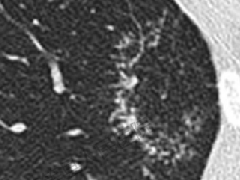

范围从小的微结节(<4mm)(图9)到较大的离散结节(通常达1cm),以及较大的结节或肿块(图10)。后者常被描述为具有不规则或锐利边缘,通常包含支气管充气征(图11)。结节可以单发或多发,通常为实性结节或部分实性结节(图12)。虽然PET扫描对这些病变的评估显示标准化摄取值轻微升高,但结果是非特异性的,临床价值有限(图13、14)。不常见的OP类型为小结节型,包括弥漫性小叶中心型模糊结节(如在非纤维性过敏性肺炎[HP]病例中可见)和树芽征,提示细支气管感染和/或炎症。

图9 微小结节。同一患者的高分辨率CT轴位扫描切面(A)和最大密度投影图像(B)。CT扫描图像显示双肺多发小实性结节,提示可能的恶性肿瘤或感染。CT扫描引导下的针吸活检结果与机化性肺炎的诊断一致。